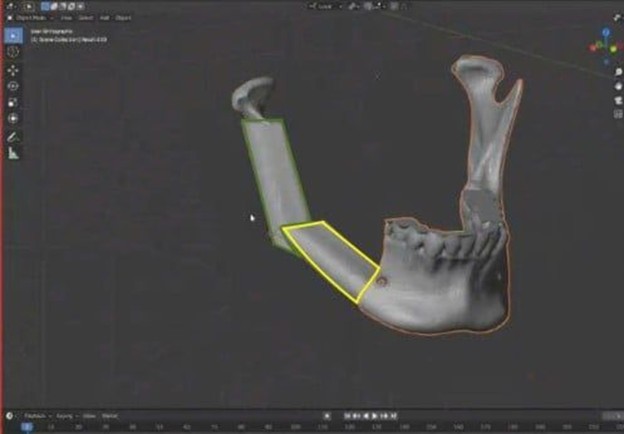

Việc ứng dụng công nghệ tái tạo 3D là một bước tiến rất quan trọng cho phép xác định phẫu thuật một cách chính xác khi cắt các khối u xương hàm dựa trên mô hình 3D đã in sẵn. Bên cạnh đó người bệnh cũng được tái tạo 3D vùng xương cẳng chân nơi lấy xương mác để xác định chính xác các vị trí cắt xương tạo góc làm sao cho phù hợp với các đoạn cong của xương hàm dưới giống như thật để thay thế xương hàm dưới vừa bị cắt do khối u.

Tại Bệnh viện Nhân dân 115, bên cạnh sự phát triển mạnh trong lĩnh vực Vi phẫu, Tạo hình và Chỉnh hình, chúng tôi áp dụng thêm công nghệ kỹ thuật số 3D trong thiết kế “Template” và lập kế hoạch phẫu thuật giúp đơn giản hóa và tối ưu hóa điều trị, tăng độ chính xác, giảm thời gian phẫu thuật và cải thiện kết quả tái tạo cấu trúc xương hàm dưới.

Để tối ưu hóa kết quả điều trị, chúng tôi thiết kể mô hình giả lập trên phần mềm 3D dựa theo CT-Scan của người bệnh, giúp mô phỏng vị trí cắt đoạn xương hàm dưới và kế hoạch tái tạo bằng xương mác. Công nghệ này cho phép thiết kế chính xác máng cắt xương và hình dáng nẹp tái tạo, tạo mẫu hàm và máng hướng dẫn phẫu thuật với độ chính xác cao, an toàn.